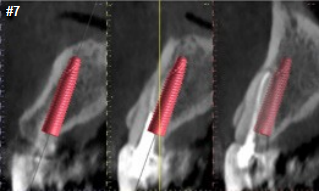

Upon prosthetic evaluation, since bothteeth were deemed unrestorable, the replacement plan an implant supported restoration. Radiographically, tooth #7 exhibited a moderate-sized periapical radiolucency.During the initial examination appointment, a CBCT and I-tero scans were obtained along with the appropriate shade to start planning an immediate non-functional tem-porary restoration. An intraoral scan was sent to the lab for digital planning of the temporary restorations.

A CBCT review showed adequate bone palatal to the socket wall, so the bone density appeared to be favorable for immediate implant placement.

Both sites were prepared into the solid palatal wall of the socket and the osteotomies were under prepared to achieve a minimum high insertion torque of at least 30N to be considered for non-functional immediately loaded temporization. 4.0x16mm implants were placed with an insertion torque above 50N at both sites. The jump gaps were grafted with cortical-cancellous allograft (Life-Net Salvin) in a dual zone fashion. The most coronal zone was packed with a moderate force to create more volume in the soft tissue compartment.

The implant must be planned and executed with a high precision as regards the position, angulation and depth in order to utilize the lab made custom temporary shells successfully.

The preferred depth of implant placement should be at least 3-4mm apical to the proposed facial gingival zenith (Linkevicius). An appropriate implant placement depth is crucial to provide adequate running room for the temporary and final restorations, a concave emergence with an adequate jump gap with the appropriate “regenerative space” (Gonzalez-martin) during dual zone grafting (Tarnow). In thin tissue phenotypes or in cases with pre-existing recession, soft tissue augmentation utilizing a connective tissue graft can be done at this time. Due to a favorable phenotype and the absence of any soft tissue defect, this case didn’t need a soft tissue graft.